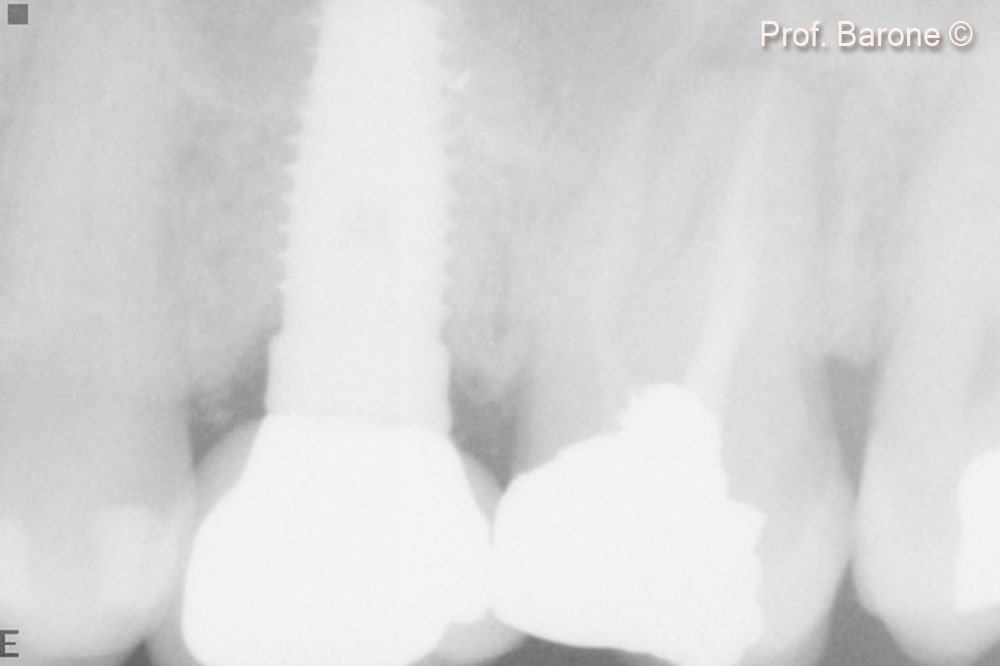

Periapical Radiograph immediately after implant placement